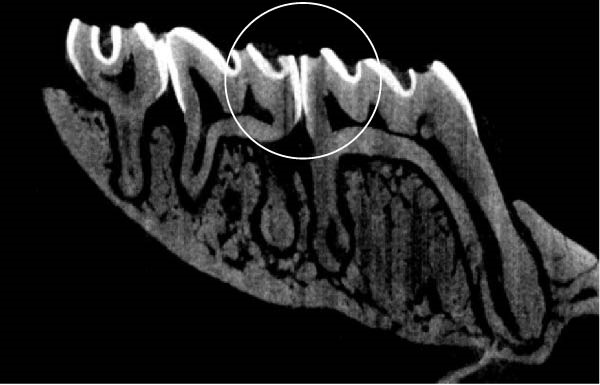

Figure 3 shows the micro‐CT images of OTM in some subgroups.

Figure 3Micro‐CT analysis of OTM after 21 and 40 days: (A) orthodontic treatment/CE injection/stress (chronic); (B) orthodontic treatment/CE injection/stress (acute); (C) orthodontic treatment/stress (chronic); (D) orthodontic treatment/stress (acute); (E) no orthodontic treatment/CE injection/stress (chronic); (F) no orthodontic treatment/CE injection/stress (acute); (G) no orthodontic treatment/no drug (chronic); (H) no orthodontic treatment/no drug (acute).(A)(B)(C)(D)(E)(F)(G)(H)